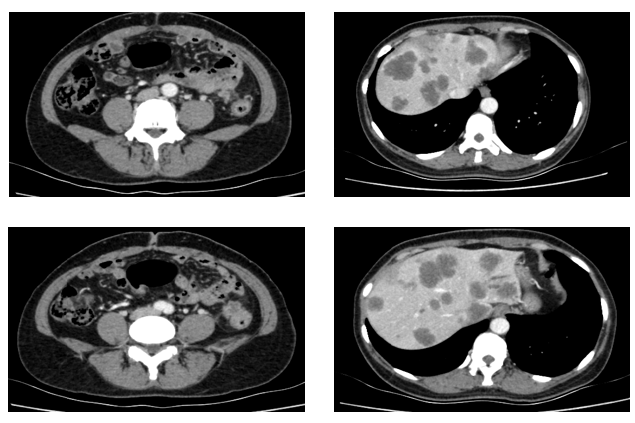

患者为51岁女性,因“间断腹痛半年余,进行性加重1月”于2021年3月就诊于我院结直肠外科。入院时胸全腹部CT(2021-3-29)提示:降结肠远端增厚,肝内多发占位,肺内多发小结节,考虑转移。肠镜检查:在距肛门28公分处,管腔狭窄,内镜不能通过。病理提示:腺癌。

于2021.04.17行“FOLFOX6”方案化疗1周期,行“奥沙利铂”化疗时,出现严重过敏。因患者基因状态为RAS,BRAF野生型,第2周期始给予“FOLFIRI+西妥昔单抗”,在治疗过程中,肿瘤标志物持续下降,影像学也显示肝脏病灶明显缩小。疗效评价PR,在2021-09-25在局麻DSA下行“肝动脉造影并化疗灌注栓塞术”。

肿瘤初次进展(2021-11-30)

患者于2021年11月30号复查时,肺上病灶增大增多,肝脏病灶稍增大,肿瘤标志物增高,整体疗效评价PD,考虑一线治疗进展。